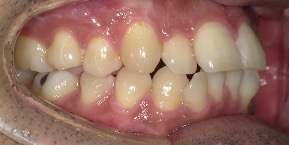

26歳女性のビフォーアフター

| 診断 | 空隙,叢生 |

| 治療方針 | 治療方針:前歯の咬合関係改善と空隙閉鎖を主な目的にて主にIPR(歯と歯の間をわずかに削合してスペースを獲得する方法)を組み込んだ動的矯正治療を行い、空隙、前歯咬合を改善後、保定を行う。臼歯部の咬合関係はプランの都合上維持することとした |

| 治療費 ※ | 69万8千円(診断、型取り、矯正中のメンテナンス、保定装置を含む料金) |

| 治療期間 | 1年8か月 |

| リスク | 1日20時間以上マウスピースを使用できない場合、歯が動かなかったり、想定しない誤差により不完全に終わる可能性がある。装着時や食事時に痛みを伴う。歯肉退縮や虫歯になるおそれがある。また、指導通りに装着できていない場合や適切なブラッシングが出来ていないとそのリスクが高くなる。歯根が短くなることがある。ごくまれに歯の神経が損傷してしまうことがある。過去にぶつけたり深い虫歯治療をしたことがあるとそのリスクはやや高くなる。矯正後には保定装置が必要。適切な使用ができない場合、後戻りの原因となる。将来的に歯並びが動いて再矯正が必要な場合がある。舌癖(舌で歯を押し出す癖)親知らずが正常に生えていない場合、その可能性がやや高くなる。 |